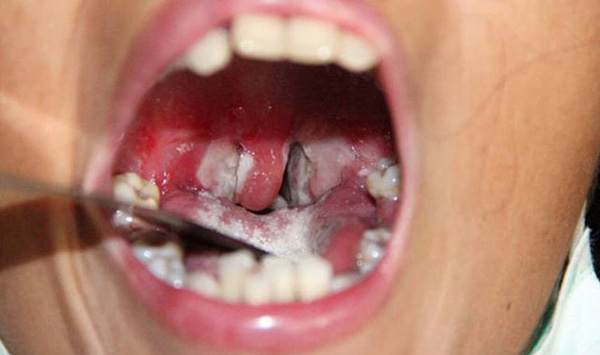

Biểu hiện bệnh có thể từ nhẹ đến nặng, thường có giả mạc màu trắng ở tuyến hạnh nhân, hầu họng, thanh quản, mũi, có thể xuất hiện ở da, kết mạc mắt, trường hợp nặng có thể gây biến chứng và tử vong. Tỷ lệ tử vong khoảng 5-10%. Bệnh bạch hầu có thể phát triển thành dịch nhất là ở trẻ dưới 15 tuổi chưa được gây miễn dịch đầy đủ. Cần lưu ý phân biệt với bệnh viêm họng có giả mạc mủ khác hoặc viêm amidan có hốc mủ.